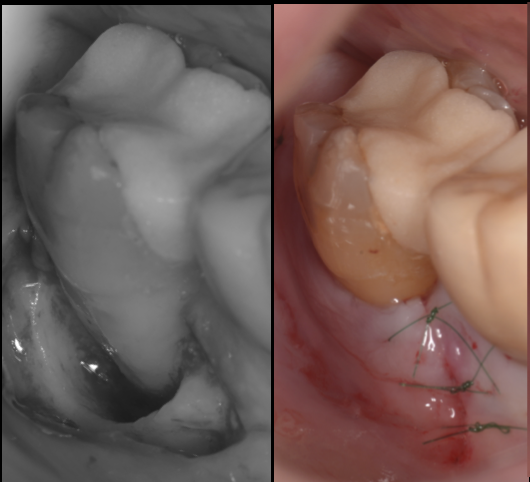

【池袋・親知らず抜歯】